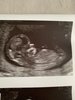

Jestem w czwartej ciazy, po 3 wczesnych poronieniach w 5-6 tc (pełna diagnostyka moja i męża, nic nie wyszło, jestem teraz na pełnym zestawie lekow: zwiększona dawka kwasu foliowego, sterydy, heparyna, progesteron i inne).

Aktualnie jestem w 11 tygodniu (10+4) więc jeszcze tak daleko nie zaszłam

Om 10.06, termin wyznaczony na 16.03, jest ktoś podobnie?